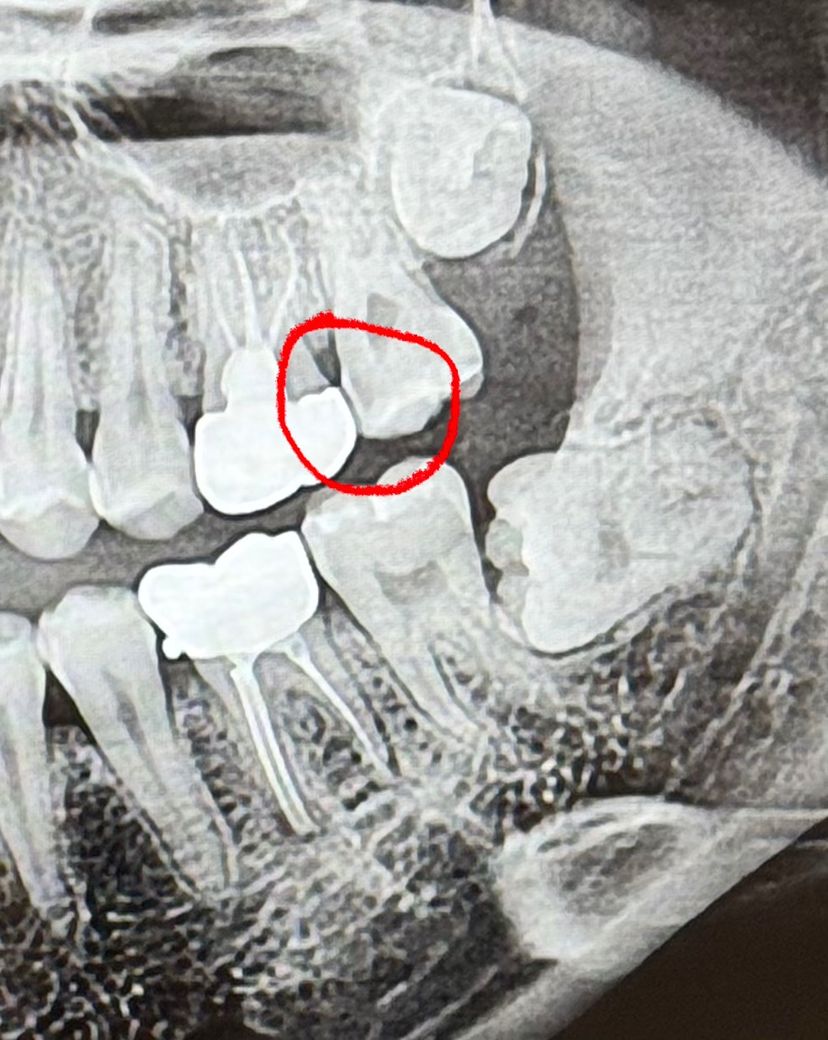

빨갛게 동그라미 친 부분 혹시 충치일까요? 실제로 보기에는 별 이상없어보이는데 엑스레이에서 조금 어둡게 나왔다고 그래서... 궁금합니다

1. 크라운이랑 겹쳐있다보니 음영이 생긴 것 같기도 하지만 인접면 충치일 가능성도 있습니다.

2. 치근단 엑스레이 사진찍고 여러 각도로 보면 좋을 것 같습니다.

3. 아래 크라운 훅도 제거해주면 좋을 것 같습니다